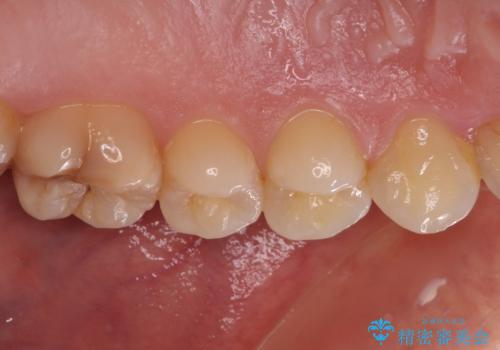

根管治療を行った奥歯は、再発防止や残された歯質を守るため、クラウンによる補綴治療が必要となります。

補綴後6ヶ月経過しレントゲンを撮影したところ、根尖周辺の病変が消失していることが確認できました。